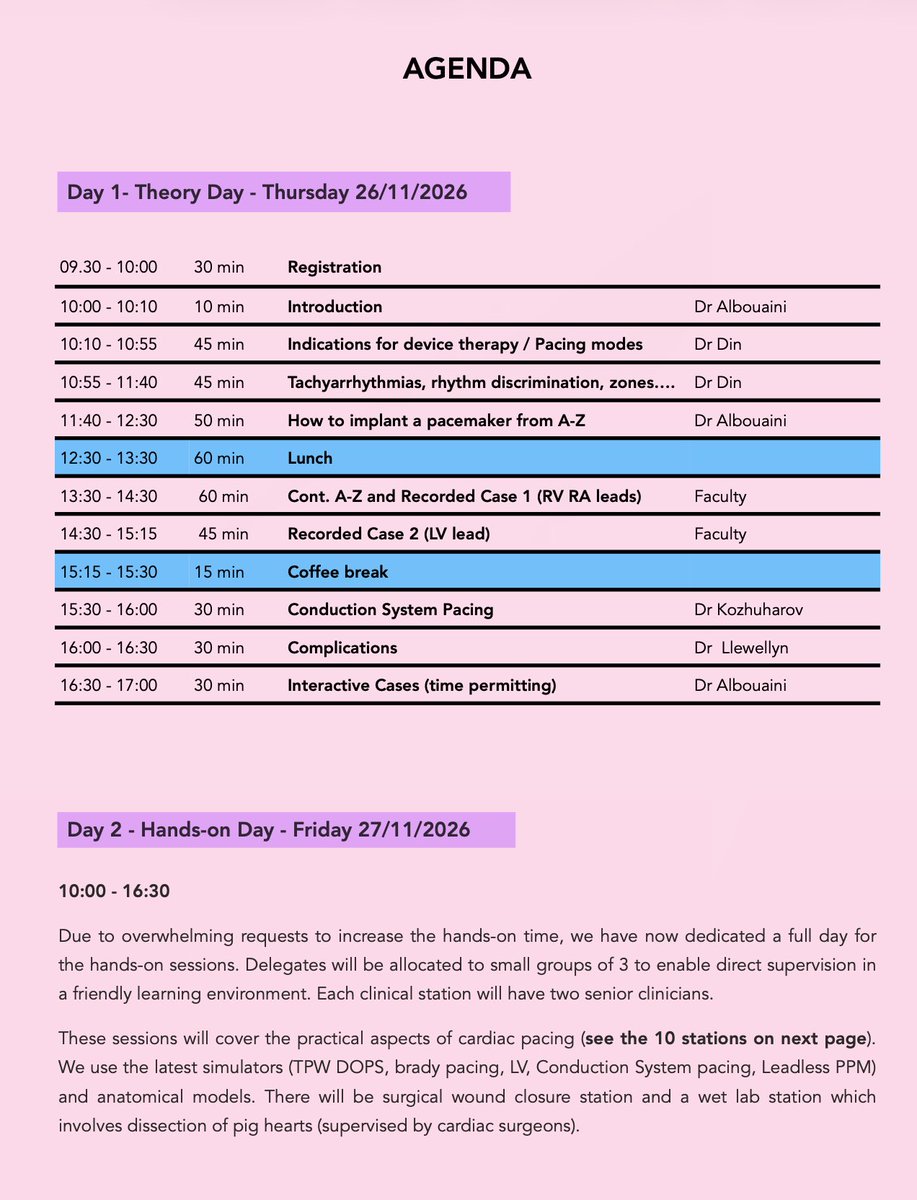

The 14th edition of our National Hands-on Cardiac Pacing Course, scheduled for Thursday -Friday 26-27/11/26. See the overwhelmingly positive feedback (pages 5-8) on PDF flyer: cardiologycases.co.uk. #MedTwitter @BritishCardioSo @TheBJCA @BHRSociety #CardioEd #CardioTwitter